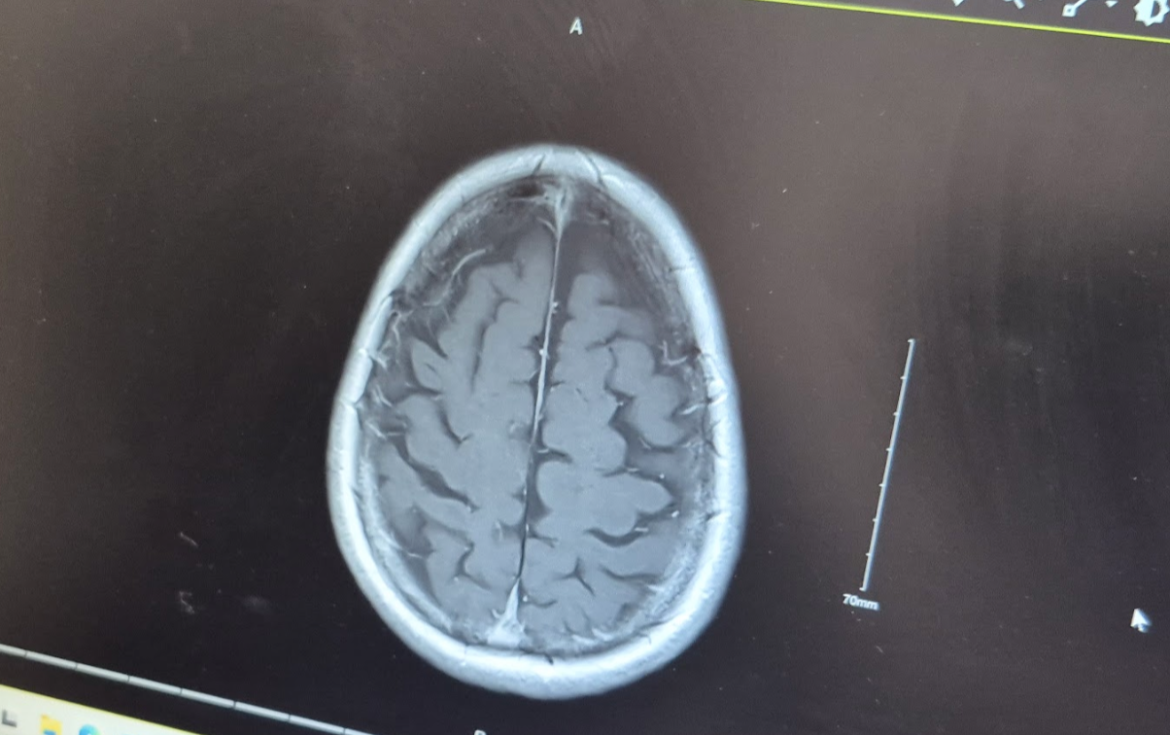

So, in order not to burden everybody with TMI, let me sum up. The scan of the inner ear revealed nothing structurally diagnostic to be going on in there, which was both a relief and (next thought) a bit mysterious. The brain scan that the hospital then sent me off to get last November was to confirm that there was nothing wrong with the way the auditory nerve—the cranial nerve that communicates with the brain on that side—was interfacing with the brain proper. Doctor Amy told me that they were looking for a relatively rare sign of swelling or hypertrophy of the nerve, which can cause hearing problems: but they found nothing.

It’s a 1.5cm meningioma in the left temporal lobe—a tumor of the meninges, one of the “containers” of tissue that hold the brain inside them.

Even from this not terribly tightly-focused imaging, it was apparently immediately clear to the radiologist reading the brain-scan MRI that the meningioma was NOT at this point dangerous. As more detailed diagnosis of such a problem isn’t in their specific specialty area, RVEEH will be forwarding this imaging to their colleagues at the neurology end of Beaumont Hospital in Dublin for further evaluation; and they (if they think it’s necessary) will pull me in for more imaging and an evaluation of what further action, if any, should be taken.